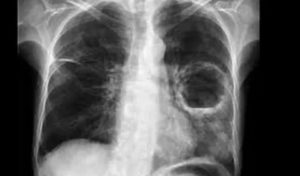

Абсцесс – еще одно гнойное заболевание легких. Это полость, окруженная капсулой из грануляций, фибрина и соединительной ткани. А внутри находятся экссудат и расплавленная ткань в виде гноя. Вокруг очага имеется реактивная инфильтрация или обусловленная предшествующей пневмонией.

- сделать рентген грудной клетки;

После попадания возбудителя в воздухоносные пути может начаться процесс воспаления ткани и отмирания клеток на определенных участках органа (абсцесс легких).

- Период формирования =напрямую зависит от причины и иммунитета организма. В среднем он продолжается от 3 дней до 3 недель.

- Следующий этап – вскрытие полости с гноем и отток мокроты через бронхи.